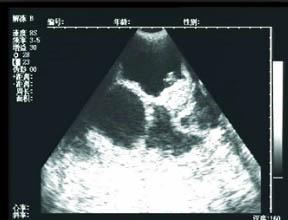

42天时去做第一次b超,就发现了有一点不对的地方,就是孕囊在左宫角那里,也许很多人,还不太了解,就是还没有到最里面,宝宝就在那里扎根了,如果乐观长长就进去了,如果不乐观,医生说就证明自己怀孕过。当然医生也不能说的那么绝对,就说明天再来一次,有专家来,再给看看。谁知这一来二去做了4次b超,让本来担心的小小,越来越担心了,心情也不再好了,这几天就哭了好几回,医生说先回家视察,只要不出血,就没有什么问题,再大一点再来视察,最主要的就是心情了。